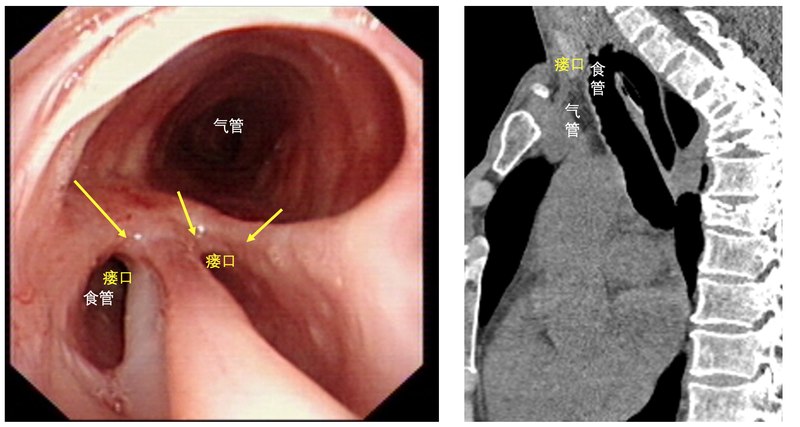

一位中年男患,因?yàn)橹灰燥埡人紩?huì)嗆到氣管里去,所以不能用嘴吃喝,只能每天把營養(yǎng)液從插在鼻子里的胃管打到胃里當(dāng)飯吃。俗話說民以食為天,不能吃飯的痛苦可想而知,而這位患者已有足足半年多的時(shí)間只能通過這個(gè)方式進(jìn)食。當(dāng)他千里迢迢來找上海市肺科醫(yī)院段亮主任看病的時(shí)候,顯得明顯的憔悴和消瘦。他所患的疾病在醫(yī)學(xué)上稱作氣管食管瘺,而這個(gè)病大有來頭。原來,半年多前,該患者因?yàn)橥话l(fā)破傷風(fēng)被緊急送往了當(dāng)?shù)蒯t(yī)院的急診科實(shí)施搶救。急診醫(yī)生為了搶救生命,立即將患者的氣管切開插管,接上呼吸機(jī)通氣。雖然搶救成功,患者也因此起死回生,逐漸恢復(fù)了自主呼吸,但搶救的結(jié)果并非圓滿。因?yàn)榛颊呔S持氣管插管的狀態(tài)先后長達(dá)1月,他的氣管在經(jīng)歷長期的擠壓后出現(xiàn)了局部的缺血壞死,最后長成了一個(gè)和鄰近的食管相通的“大窟窿”。當(dāng)他被確診為氣管食管瘺的并發(fā)癥時(shí),他被告知,如果不接受治療,他只能終生依賴胃管進(jìn)食。不幸的是,當(dāng)?shù)蒯t(yī)院沒有治療的條件。這句話讓這位正值壯年的男性陷入了沉思。不是他不感謝讓他重獲新生的醫(yī)院,而是終生殘疾的代價(jià),對(duì)一位需要供養(yǎng)全家老小的男人來說實(shí)在太大。氣管食管瘺由于涉及到氣管和食管兩個(gè)器官,本身就屬于疑難病癥。小的氣管食管瘺,尚可以通過內(nèi)鏡放置支架的方法使其自然愈合,但正如本例所患的巨大氣管食管瘺(圖1)只能通過手術(shù)治療,而且瘺口越大,手術(shù)難度也越大,越難保證手術(shù)是否成功,或者成功解決瘺的問題以后是否會(huì)并發(fā)二次損傷,就像患者上次氣管插管后出現(xiàn)瘺一樣。再加上患者先前有過氣管切開的經(jīng)歷,手術(shù)當(dāng)中處理氣管時(shí)還要兼顧氣管食管瘺和氣管切開處瘢痕兩個(gè)問題,對(duì)于外科醫(yī)生來講具有十足的挑戰(zhàn)?;颊唠S后求助于多家醫(yī)院,都被告知手術(shù)難度太大而拒之門外,患者和家屬抱著最后的希望來到上海市肺科醫(yī)院.然而這一切并沒有難倒具有多年氣管外科診療經(jīng)驗(yàn)的肺科醫(yī)院胸外科團(tuán)隊(duì)。充分的多學(xué)科討論為患者制定了精心周密的診療方案,最后由段亮主任親自主刀為患者實(shí)施手術(shù)。手術(shù)中,段主任先是把病變的整段氣管切除,再把食管的瘺口縫上,之后將剩余的兩端氣管用縫線吻合,完成氣管的重建。最后,為了避免瘺的復(fù)發(fā),還要在原來的瘺的位置上墊襯一塊肌肉(圖2)。這些看似簡(jiǎn)單的步驟,在嫻熟的手術(shù)技巧下完成,也足足消耗了4個(gè)小時(shí)。手術(shù)后1月,患者復(fù)查氣管鏡顯示原來的瘺口已經(jīng)消失不見,取而代之的是由于肉芽增生導(dǎo)致輕微狹窄的氣管吻合口。通過氣管鏡下燒灼和球囊擴(kuò)張,狹窄的氣管就完全恢復(fù)了通暢(圖3)。自此,治療過程基本宣告結(jié)束,患者終于可以和留置半年的胃管說再見,重新開始有飯吃的生活。而這整個(gè)治療期間自付的費(fèi)用,甚至不到5萬元。正是肺科醫(yī)院氣管外科的專業(yè)技術(shù),讓患者的人生重燃了希望;也正是患者對(duì)肺科醫(yī)院的信賴,促進(jìn)了肺科醫(yī)院氣管外科的快速成長。